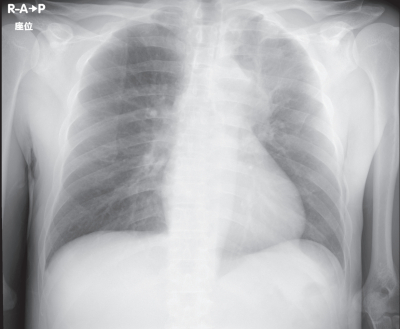

検査所見:尿所見:蛋白(-)、糖(-)、潜血(-)。血液所見:赤血球 437 万、Hb 12.3 g/dL、Ht 34 %、白血球 5,400(好中球 45 %、好酸球 21 %、好塩基球 1 %、単球 9 %、リンパ球 24 %)、血小板 23 万。血液生化学所見:総蛋白 6.3 g/dL、アルブミン 3.7 g/dL、 総ビリルビン 0.5 mg/dL、 直接ビリルビン 0.2 mg/dL、AST 43 U/L、ALT 78 U/L、LD 169 U/L(基準 120~245)、ALP 200 U/L(基準 38~113)、γ-GT 96 U/L(基準 8 ~50)、CK 100 U/L(基準 30~140)、 尿素窒素 11 mg/dL、 クレアチニン 1.0 mg/dL、 尿酸 3.7 mg/dL、 血糖 92 mg/dL、Na 118 mEq/L、K 4.6 mEq/L、Cl 89 mEq/L、Ca 8.4 mg/dL。 血清 浸透圧240 mOsm/L(基準 275~288)、 尿浸透圧 572 mOsm/L(基準 50~1,300)、 尿中Na 84 mEq/L。 胸部エックス線写真と胸腹部造影 CTを別に示す。